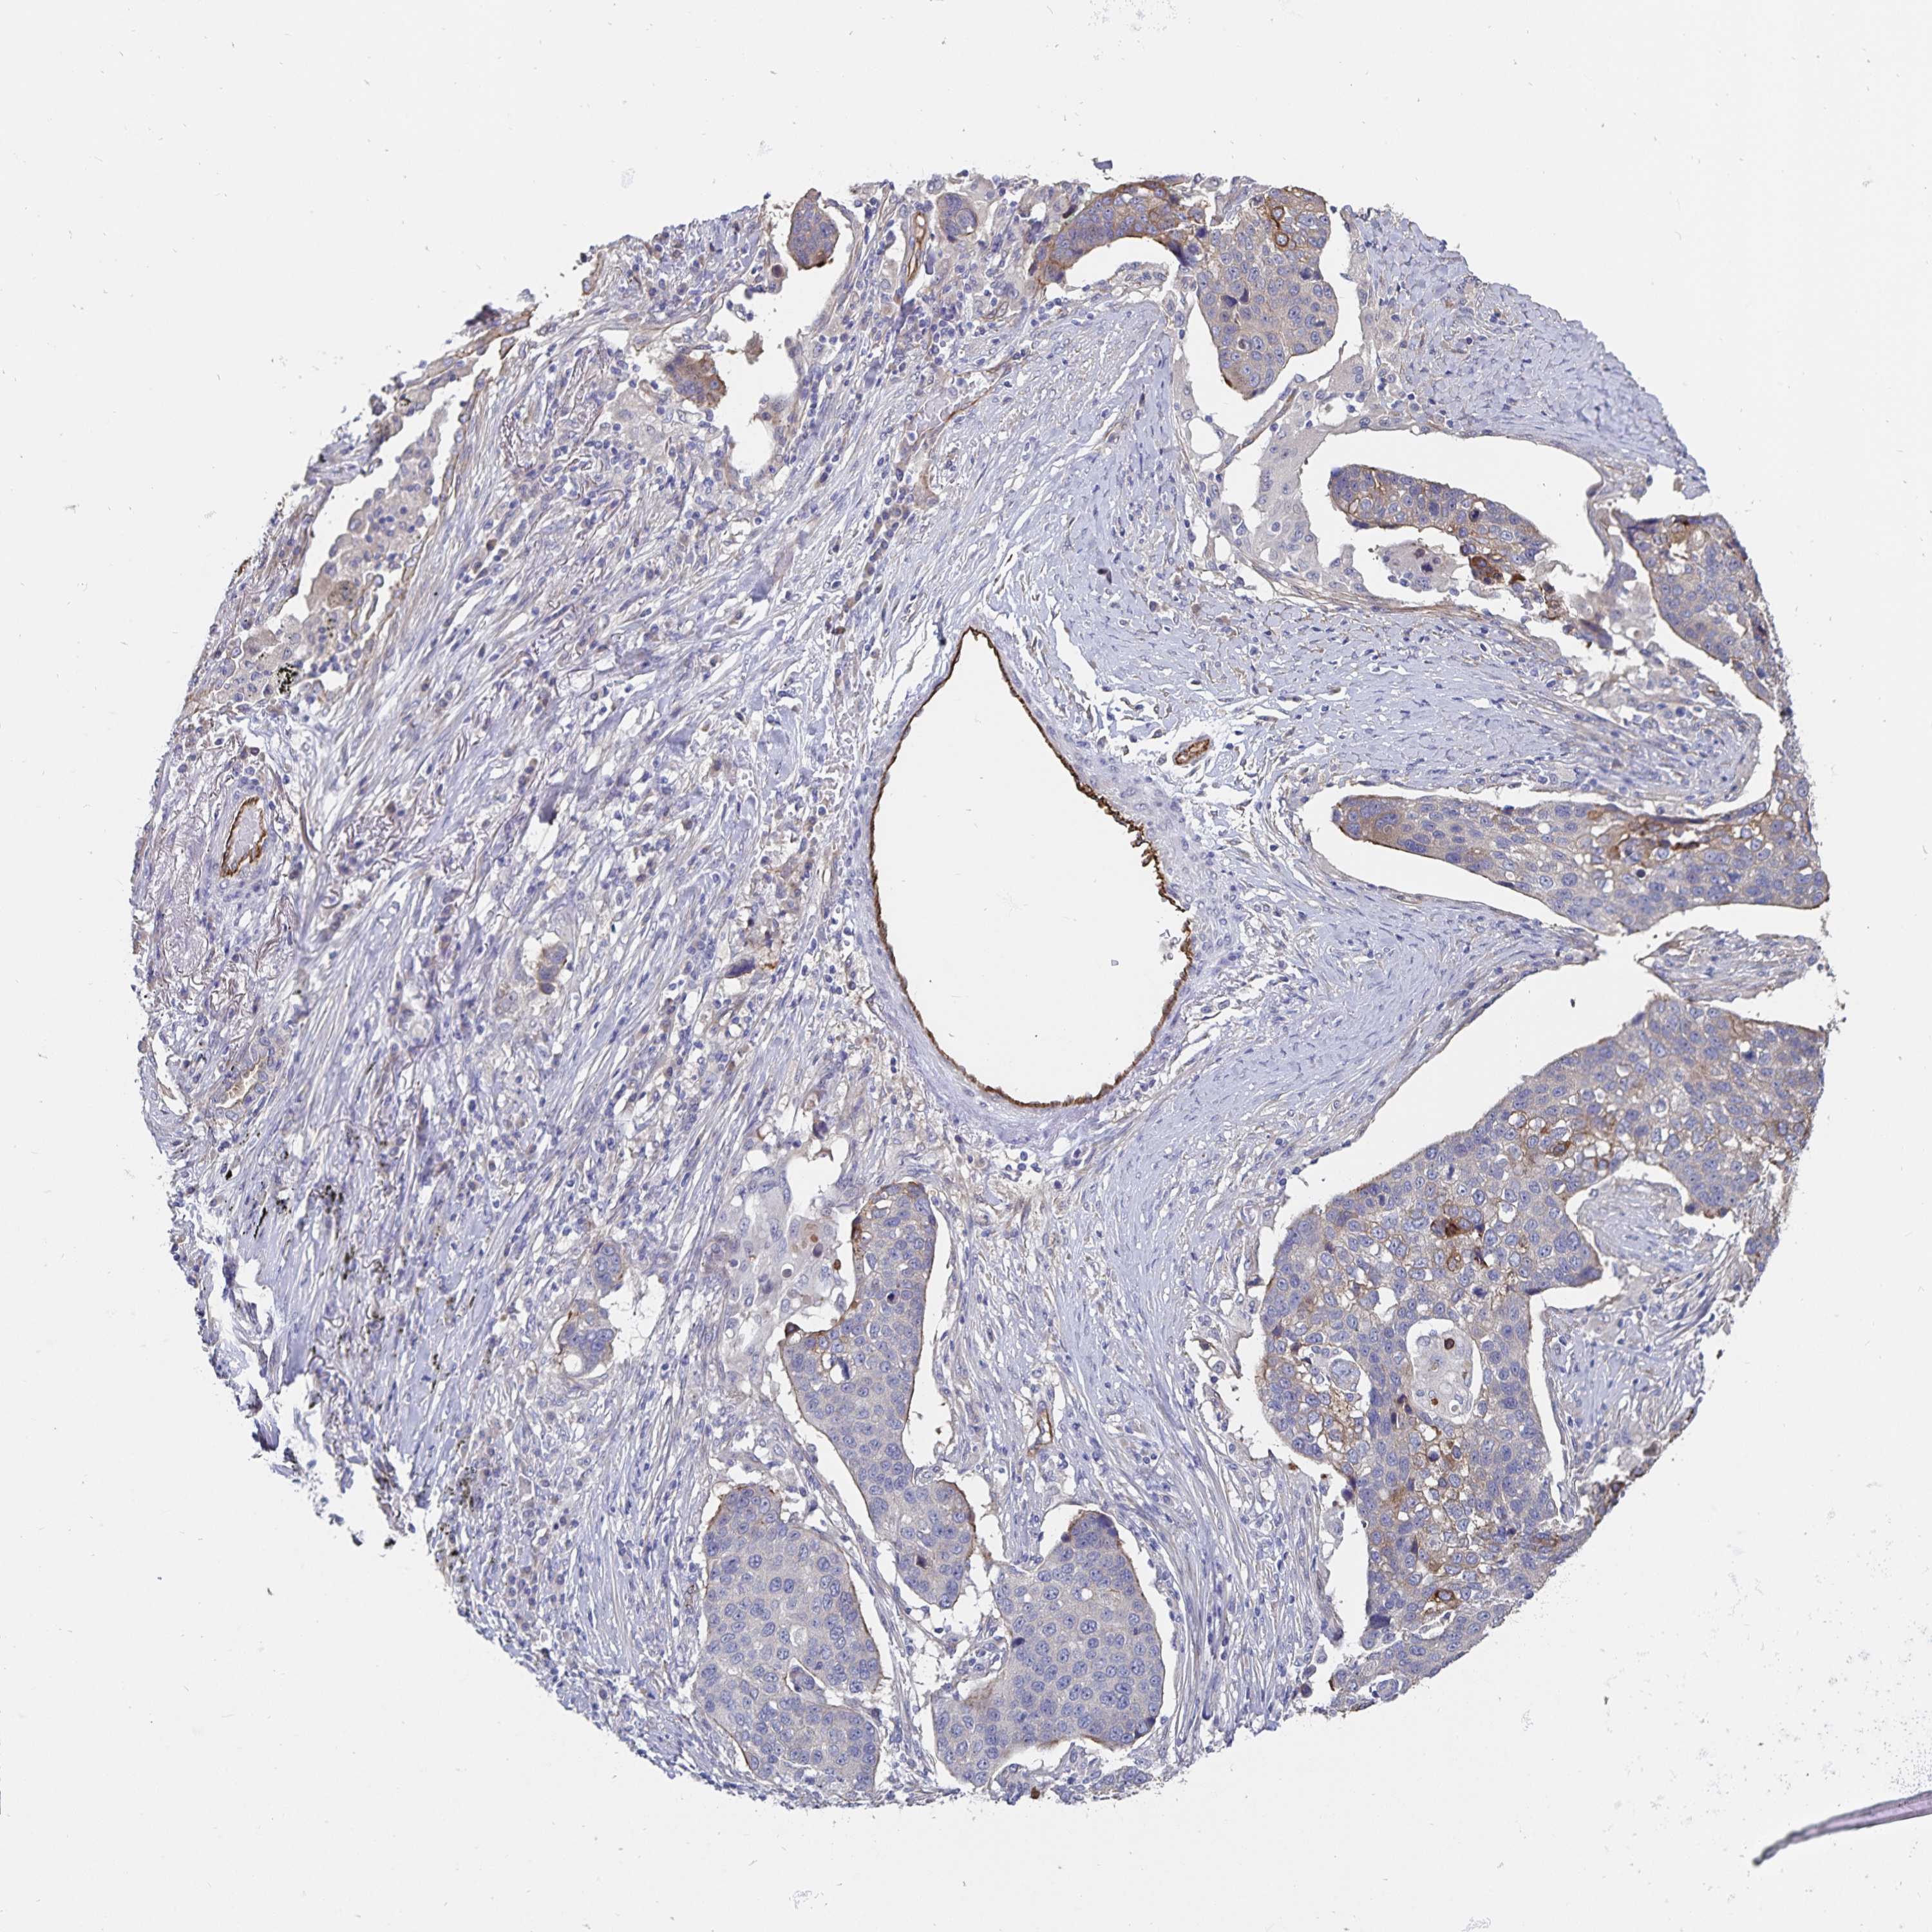

CANCER LUNG CANCER Show tissue menu

Lung cancer

Human cancer

SSTR1 is not prognostic in Lung Adenocarcinoma (TCGA)

SSTR1 is not prognostic in Lung Adenocarcinoma (validation)

SSTR1 is not prognostic in Lung Squamous Cell Carcinoma (TCGA)